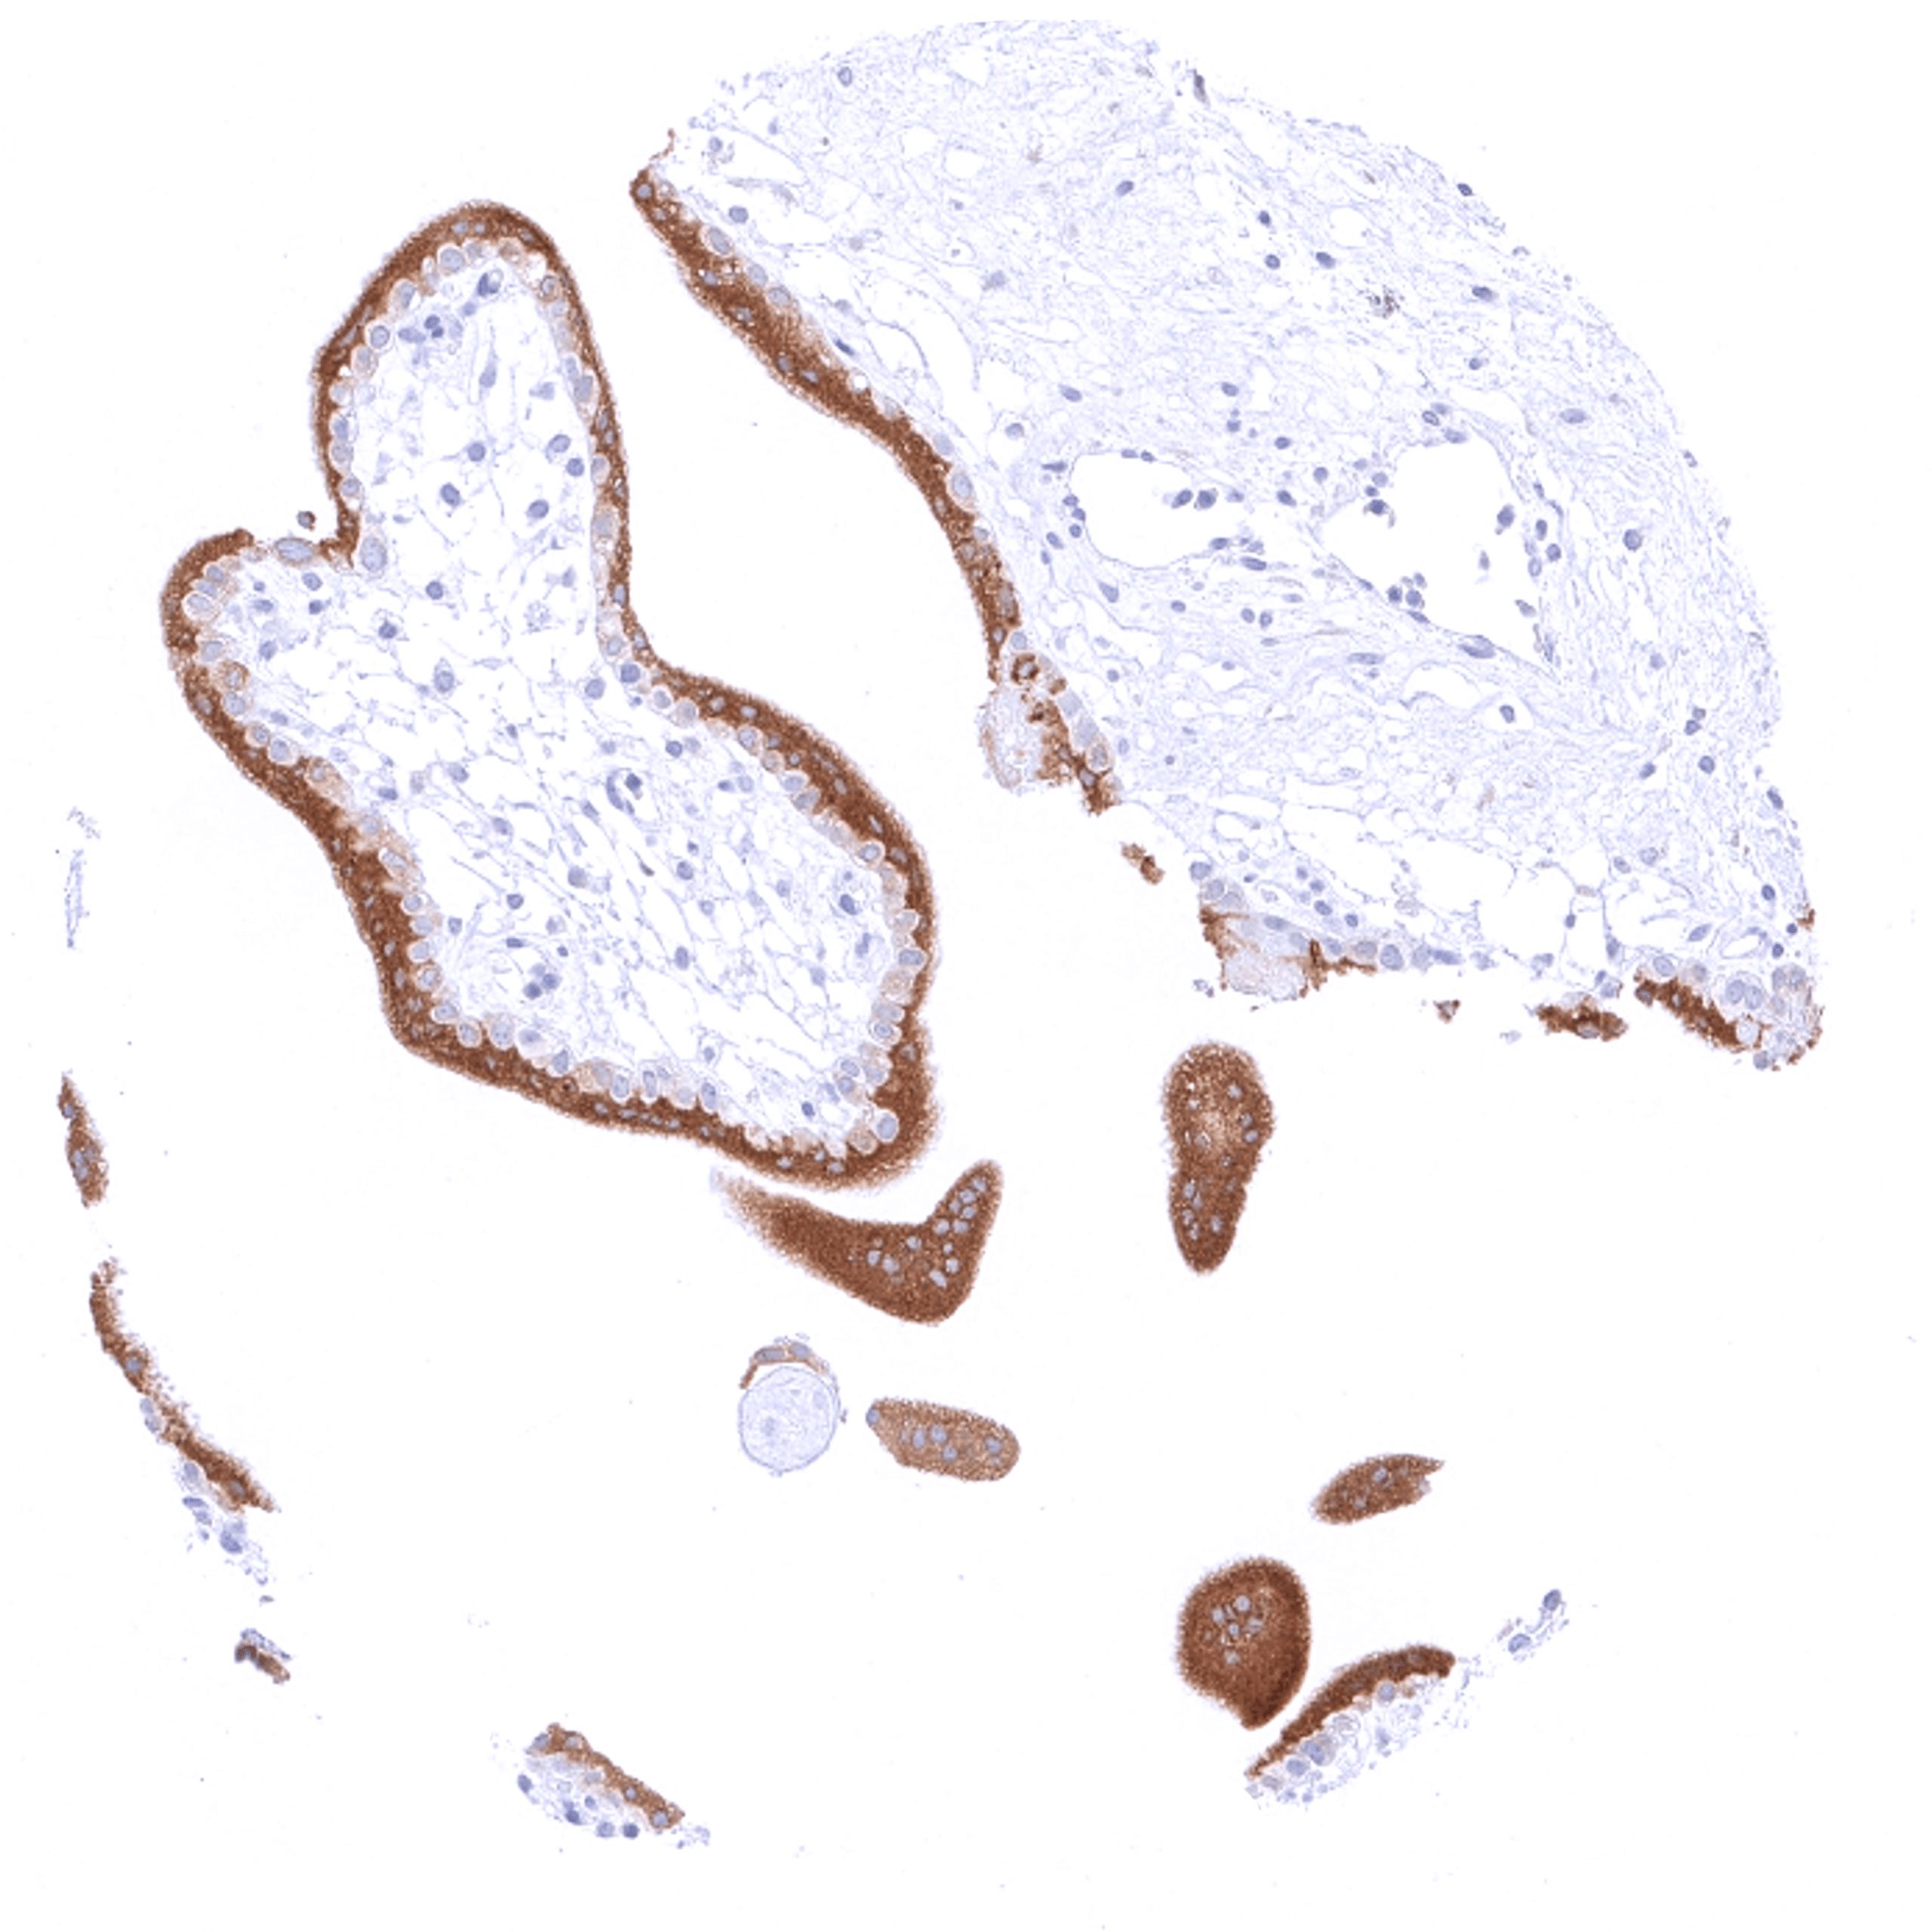

| Male genital | Prostate | Weak to moderate bcl-2 staining of basal cells. |